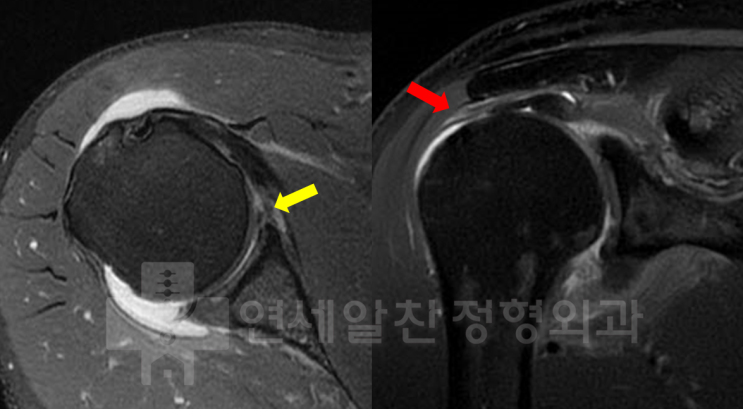

어깨 석회, 주사치료 vs 충격파 vs 석회분쇄흡입술 비교

안녕하세요. 정형외과 전문의 이동규원장 입니다. "석회성건염이라는데, 주사 맞으면 되나요?" &...